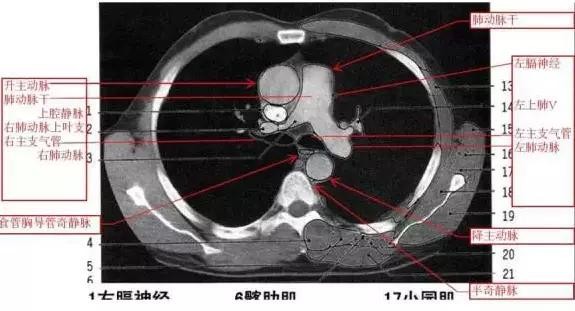

详尽的胸部CT影像示意图

胸部的CT是通过X线计算机体层摄影(CT)对胸部进行检查的一种方法。正常胸部CT层面较多,每一层面结构所表现的图像不同。下面是胸部CT图文示意图,可帮助临床医生详细了解CT结构。我们一起来看一下吧。

来源:影像论坛